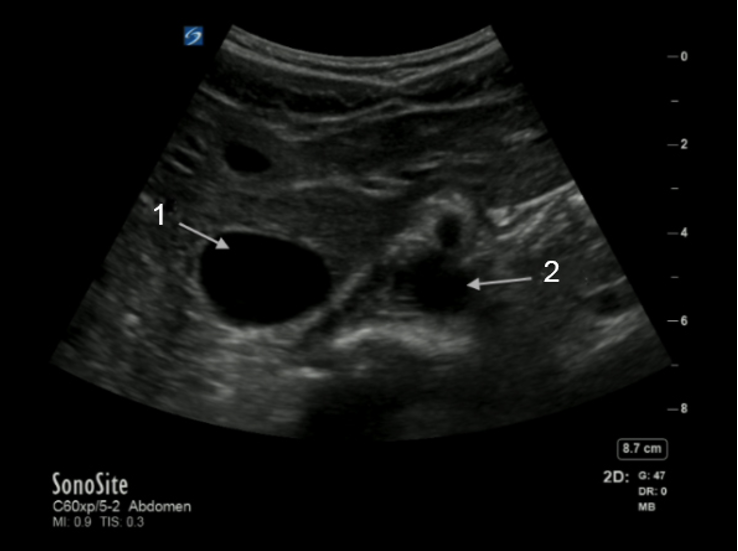

Aorta and Inferior Vena Cava (IVC) Transverse Image

Inferior Vena Cava (IVC)

Aorta